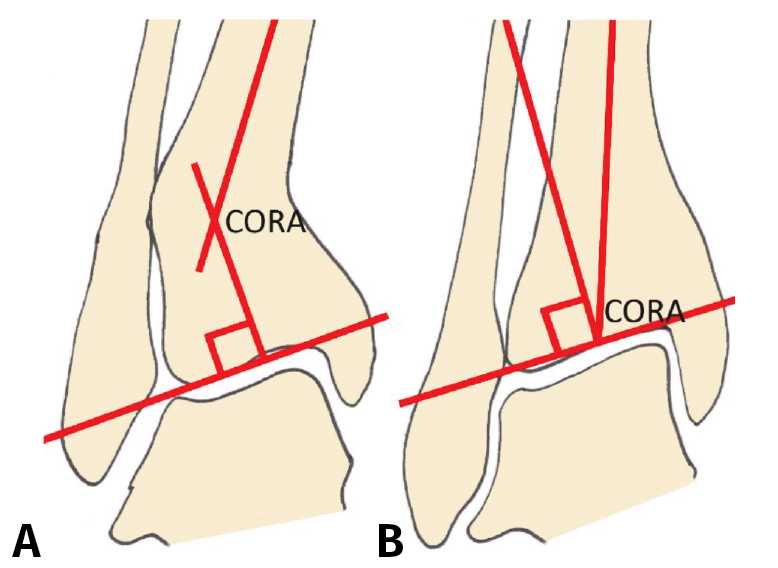

Figura 1. A: ángulo tibial distal lateral (LDTA). Está formado por la superficie tibial articular distal y el eje anatómico de la tibia; B: ángulo tibial distal anterior (ADTA). Está formado por el eje mecánico de la tibia y la línea articular; C: ángulo tibio-talar. Está definido por la orientación de las superficies articulares de la tibia y del astrágalo en el tobillo.

Debe incluir la radiología convencional (siempre en carga) dorsoplantar y lateral de ambos pies, anteroposterior y lateral del tobillo y la proyección de Saltzman. En el caso de haber apreciado deformidades en el miembro, solicitaremos también ambas extremidades completas. En el plano sagital (Figura 1), mediremos el ángulo tibial distal anterior (ADTA, por sus siglas en inglés). Este está formado por el eje mecánico de la tibia y la línea articular, y mide 80 ± 3° en la extremidad normal. Un aumento del ADTA representa una deformidad en recurvatum. En el plano coronal (Figura 1), se valora el ángulo tibial distal lateral (LDTA, por sus siglas en inglés), el ángulo tibio-talar y la alineación calcáneo-tibial. El LDTA(34) está formado por la superficie tibial articular distal y el eje anatómico de la tibia, y mide 89 ± 3°. La alineación calcáneo-tibial (medida en la proyección de Saltzman) es muy útil para confirmar la presencia de deformidades en varo o valgo, así como para valorar la compensación de un LDTA anormal (la articulación subastragalina puede compensar hasta 15° de eversión y 30° de inversión). Si tenemos un ADTA o LDTA anormal (deformidad sagital o coronal), debemos medir el center of rotation of angulation (CORA). Es la intersección entre la línea mediodiafisaria y la línea que comienza en el centro de la articulación y perpendicular al anormal ADTA o LDTA. El CORA puede estar localizado en la línea articular o proximalmente (Figura 2).

Figura 2. Medición y determinación del center of rotation of angulation (CORA). A: CORA supramaleolar; B: CORA en la articulación.